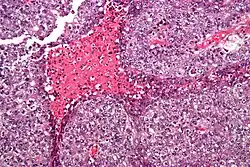

Embryonal carcinoma. H&E stain.

The gross examination usually shows a two to three centimetre pale grey, poorly defined tumour with associated haemorrhage and necrosis.[3]

The microscopic features include: indistinct cell borders, mitoses, a variable architecture (tubulopapillary, glandular, solid, embryoid bodies – ball of cells surrounded by empty space on three sides), nuclear overlap, and necrosis.

Solid (55%), glandular (17%), and papillary (11%) are the most common primary patterns (predominant architectural pattern occupying at least 50%). Other less common primary patterns included nested (3%), micropapillary (2%), anastomosing glandular (1%), sieve-like glandular (<1%), pseudopapillary (<1%), and blastocyst-like (<1%).[4]